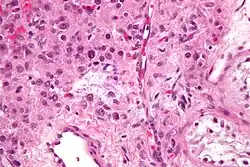

W obrazie mikroskopowym są widoczne rozległe obszary martwicy i obszary krwotoczne, a obszary z żywą tkanką nowotworową mogą być niewielkie[110]. Czasami guz ulega w całości martwicy i w miejscu guza pierwotnego obecna jest jedynie blizna[111]. Utkanie guza w różnych proporcjach tworzą komórki syncytiotrofoblastu i cytotrofoblastu[109]. Komórki syncytiotrofoblastu są duże, wielojądrzaste, nieregularnego kształtu, jądra są nieregularnego kształtu, hiperchromatyczne, komórki zawierają obfitą ilość eozynofilnej do amfifilowej cytoplazmy[109][111]. Komórki cytotrofoblastu są jednojądrzaste, wielobocznego kształtu, mają amfifilową cytoplazmę, cechują się łagodnym do umiarkowanego pleomorfizmem jądra komórkowego[110][111].

W lepiej zróżnicowanych obszarach guza gniazda komponentu cytotrofoblastycznego są przykryte przez komponent syncytiotrofoblastyczny, co może przypominać utkanie widoczne w niedojrzałych kosmkach łożyska[109][110]. Poza tym obserwuje się przypadkowe mieszanie się obu tych komponentów[110]. Rzadko obserwuje się jedynie składnik cytotrofoblastyczny, a komponent syncytiotrofoblastyczny jest w niewielkim stopniu reprezentowany[109]. Cytotrofoblast wykazuje wysoką aktywność mitotyczną, podczas gdy syncytiotrofoblast jest nieaktywny mitotycznie[110]. Inwazja naczyń jest wyraźna i częsta[109].